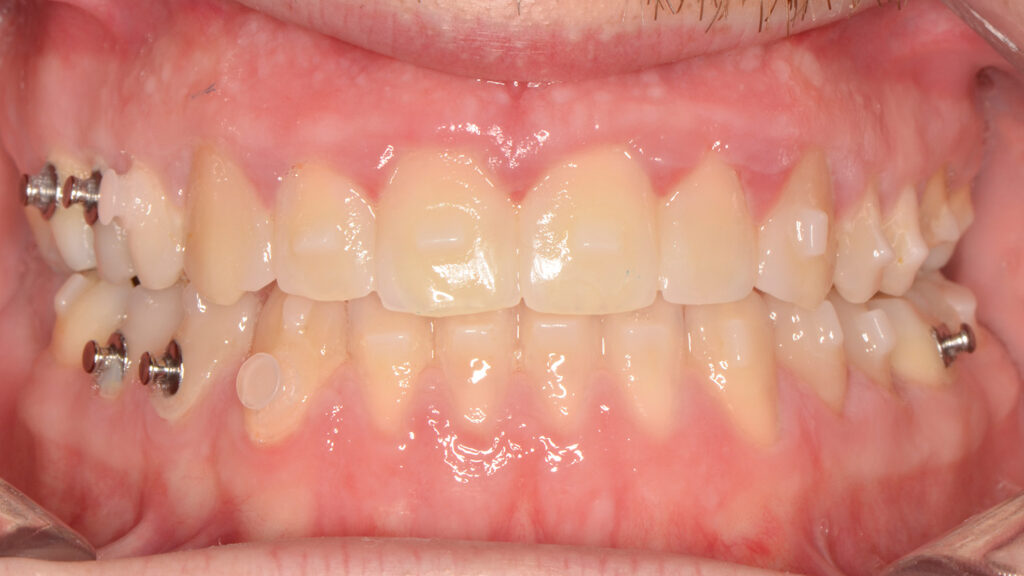

Intraoral examination showed an Angle Class III relationship on both sides, along with an anterior open bite. Additionally, a narrow maxilla with a bilateral posterior crossbite was observed.

Once the transverse discrepancy was corrected, treatment continued with Spark Aligners to address the vertical plane. The planned vertical correction involved extruding the upper anterior teeth, with 1.7 mm of extrusion in the upper arch, and 1.5 mm in the lower arch using attachments. To assist in bite closure, turbo bites were employed to intrude the mandibular molars.

As shown in the accompanying images, the planned vertical correction was fully achieved. At this stage, provisional composite veneers were placed from canine to canine in the upper arch to enhance the patient’s aesthetics and compensate for Bolton’s discrepancy.